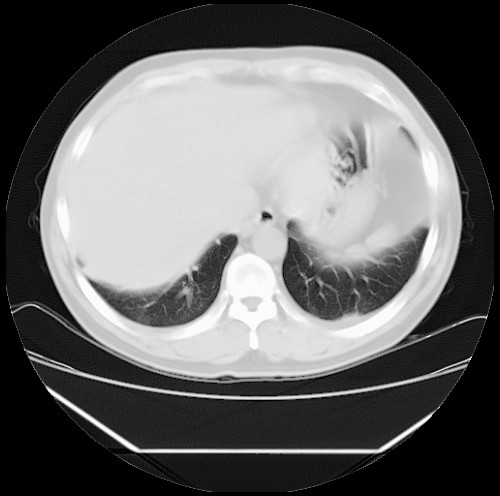

标题: CT22085:双肺多发结节

男,44岁,咳嗽,痰中带血2天。

病灶大部分位于胸膜下,结节大小相差不是很大,肺尖太干净。这种结核没见过,我认为可排除。

首先考虑转移,不除外肉芽肿、真菌感染。建议查其它。

除肺内及胸膜下可见多发大结节外,在肺小叶中心核、小叶间隔及支气管血管束上亦可见多方小结节,可以认为是随机分布。考虑转移可能性大。

仔细观察病灶形态,病灶边界部分清楚,结合临床症状,首先考虑转移,纵隔内多个肿大淋巴结影。

双肺血管纹理末端多发类圆形结节,边界光滑清晰 气管前腔静脉后淋巴结肿大

考虑转移瘤

本例双肺多发类圆形高密度灶,边清,结合病史多考虑双肺多发转移改变,可以结合实验室检查。